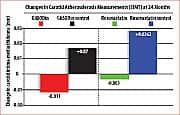

About a year and a half after commencing daily supplementation with GliSODin®, measurable decreases in subjects’ IMT were detected. Approximately two years after starting GliSODin® supplementation, decreases in IMT values became statistically significant. In dramatic contrast, control subjects not receiving GliSODin® experienced increased IMT values over the same period.21 There were no reported side effects in either group. This remarkable study demonstrated that reversal of atherosclerosis in adults with multiple risk factors for future cardiovascular disease is possible through a combination of healthy diet and daily intake of GliSODin® (orally bioavailable superoxide dismutase). These findings were confirmed by monitoring of clinical and biological health parameters, and measurements of carotid IMT. The GliSODin® regimen, “improves, significantly, the anti-oxidant status,” noted investigators, “and diminishes, remarkably, carotid artery IMT.”21 It should be noted that these findings echo those of other researchers, who, in previous and subsequent studies, have convincingly demonstrated GliSODin®’s ability to reduce oxidative damage in human volunteers and animal models.25-27 Pomegranate Fights Oxidative Damage, Reverses AtherosclerosisScientists have recently shown that pomegranate juice offers cardiac health benefits that complement those of GliSODin®. In the past seven years alone, the amount of published research on pomegranate has increased seven-fold over all preceding years in the medical and scientific literature.40 That’s almost certainly because each new study underscores the potential of this fruit to fight cancer and to combat oxidative stress. The latter is of particular importance for atherosclerosis prevention.